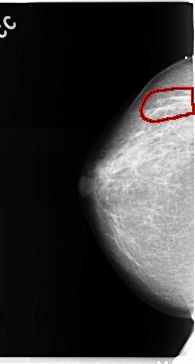

C_0110_1.RIGHT_MLO

RIGHT_CC LINES 4720 PIXELS_PER_LINE 2528 BITS_PER_PIXEL 12 RESOLUTION 50 OVERLAY

FILE: C_0110_1.RIGHT_CC.OVERLAY

TOTAL_ABNORMALITIES 1

ABNORMALITY 1

LESION_TYPE MASS SHAPE ARCHITECTURAL_DISTORTION MARGINS SPICULATED

ASSESSMENT 5

SUBTLETY 3

PATHOLOGY MALIGNANT

TOTAL_OUTLINES 1

BOUNDARY